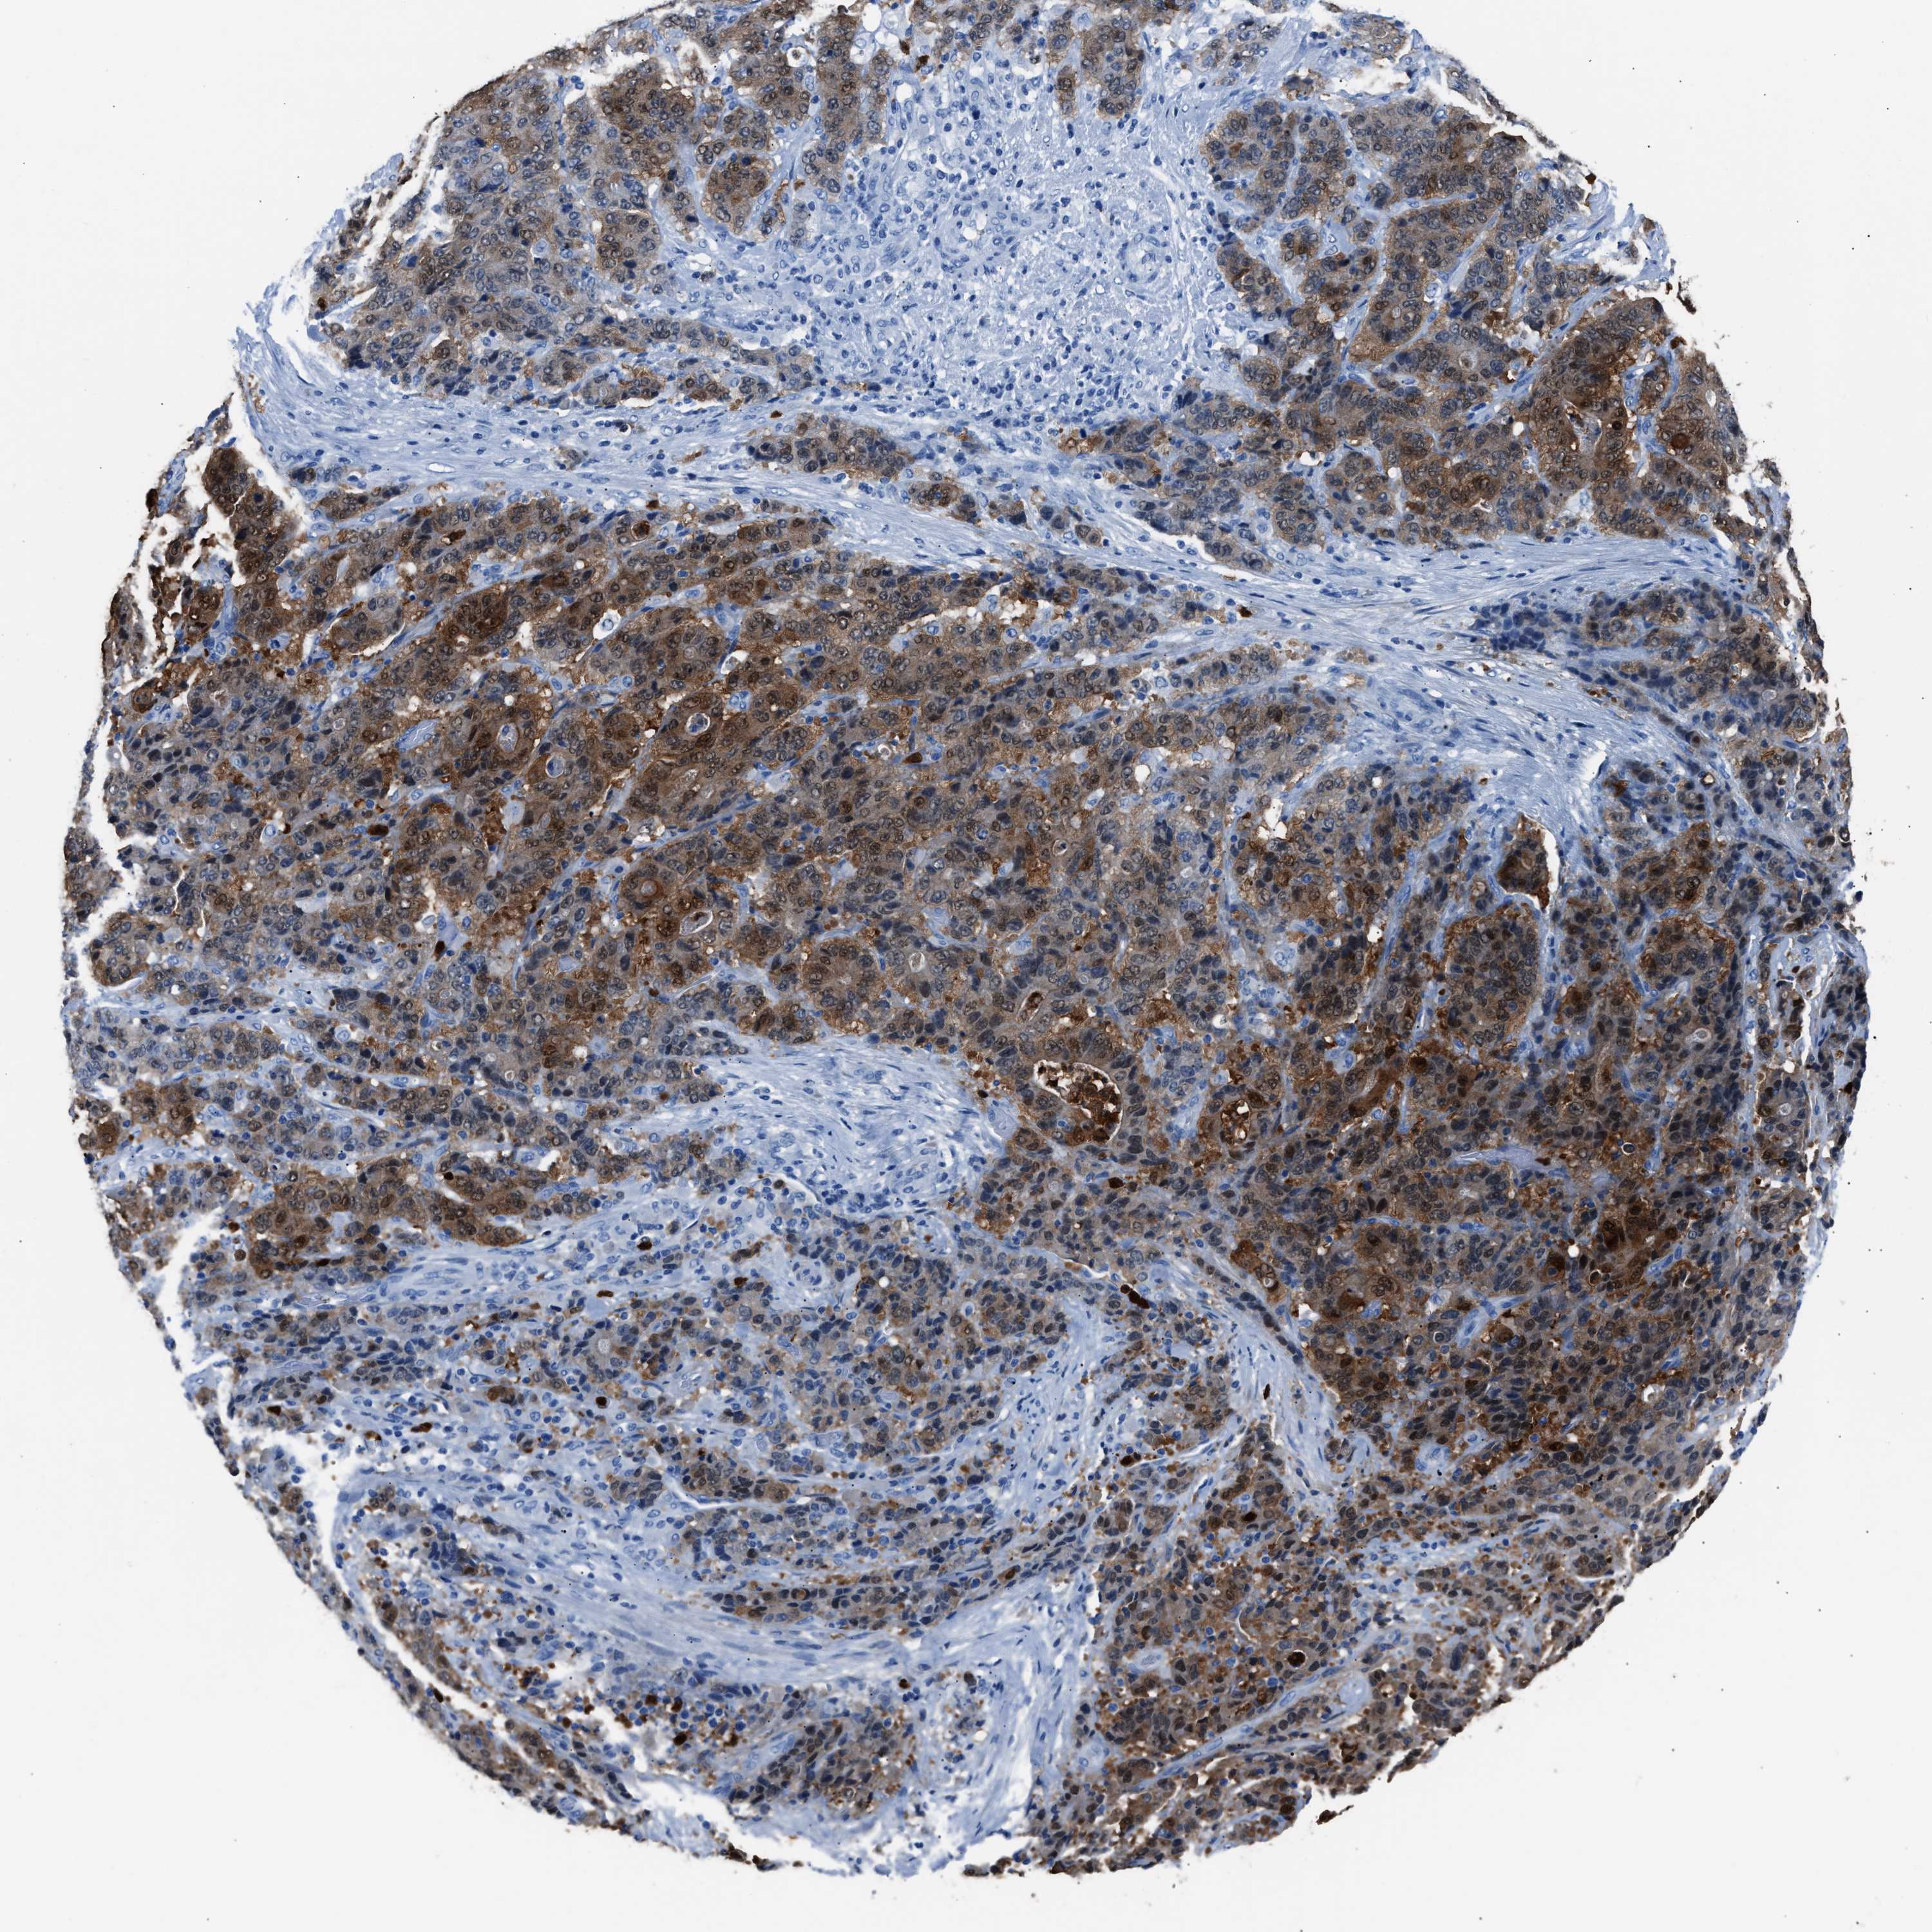

STOMACH CANCER - Protein expressioni

A mouse-over function shows sample information and annotation data. Click on an image to view it in a full screen mode. Samples can be filtered based on level of antibody staining by selecting one or several of the following categories: high, medium, low and not detected. The assay and annotation is described here.

Note that samples used for immunohistochemistry by the Human Protein Atlas do not correspond to samples in the TCGA dataset.

Antibody stainingi

Antibody staining in the annotated cell types in the current human tissue is reported as not detected, low, medium, or high, based on conventional immunohistochemistry profiling in selected tissues. This score is based on the combination of the staining intensity and fraction of stained cells.

Each image is clickable and will lead to virtual microscopy that enables deeper exploration of all samples and also displays staining intensity scores, fraction scores and subcellular localization as well as patient and tissue information for each sample.

Antibody HPA019502

Staining

High

Medium

Low

Not detected

Intensity

Strong

Moderate

Weak

Negative

Quantity

>75%

75%-25%

<25%

None

Location

Nuclear

Cytoplasmic/membranous

Cytoplasmic/membranous,nuclear

Adenocarcinoma, NOS